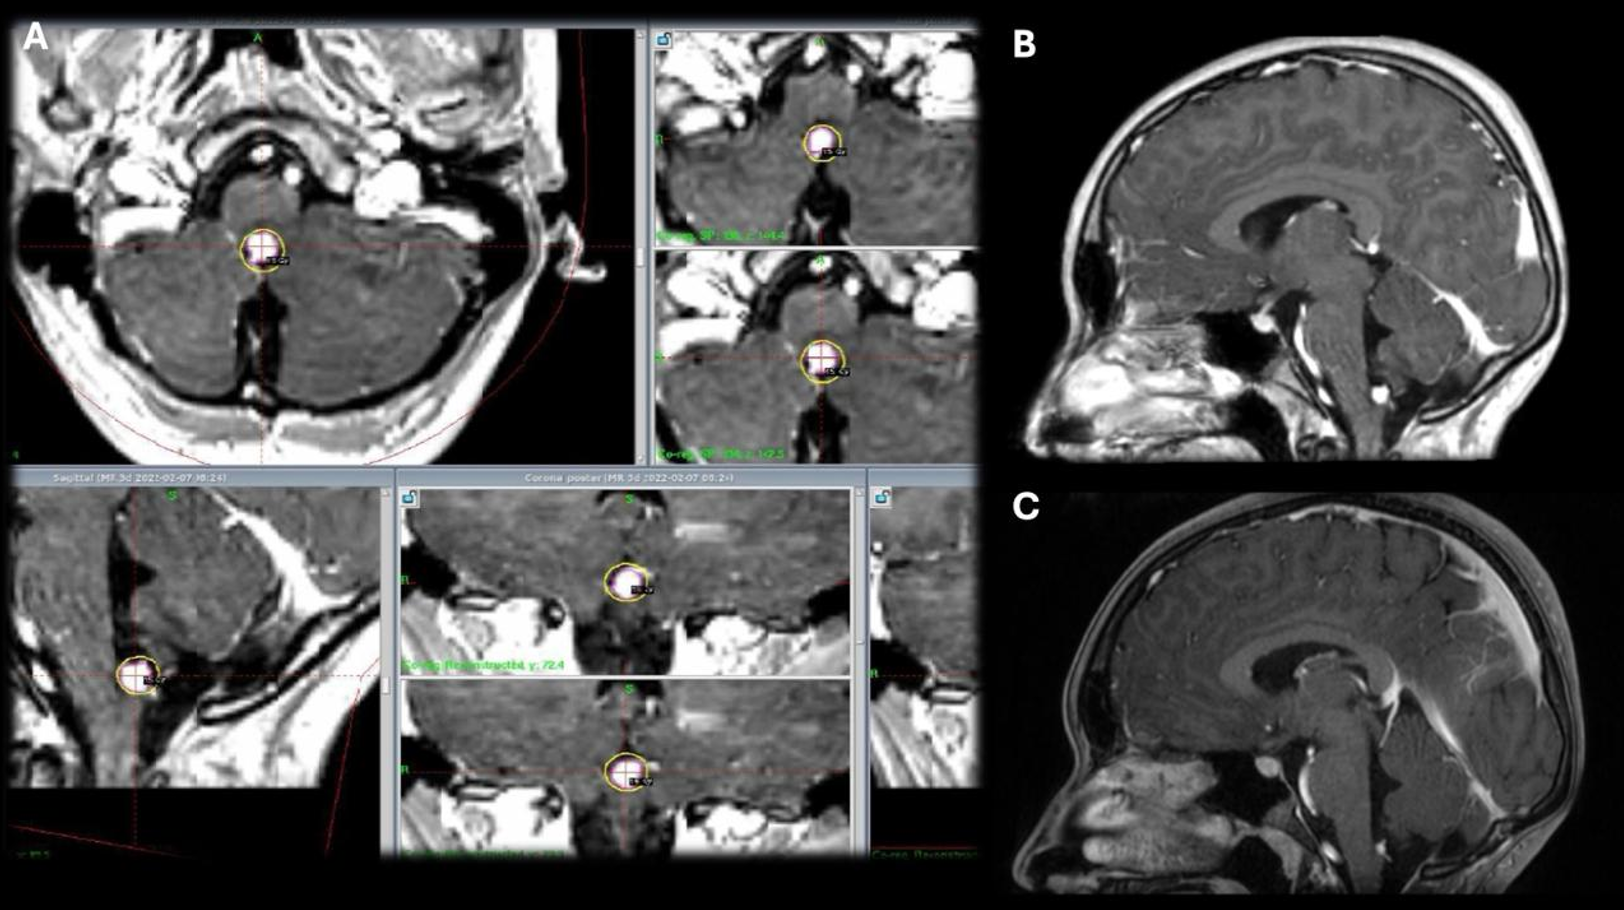

Patolojik tanılara göre değerlendirildiğinde en sık karşılaşılan tümör grubu gliyal tümörler olup, dört hastada saptanmıştır. Bu hastaların ilki 15 yaşındaki kız hasta patoloji sonucu DSÖ derece 3 gliyal kitle olarak raporlanmıştır. Cerrahi sonrası dönemde rezidü kitlesine yönelik lezyon için Karnofsky skoru düşük olması nedeniyle radyoterapi (RT) uygun görülmedi ve hastaya GKRC yapıldı. 5. ay kontrol görüntülemesinde lezyon boyutlarında artış olması ve Karnofsky skoru düzelen hastaya RT yapıldı. Hasta RT’den 2 ay sonra vefat etti. İkinci hasta 15 yaş kız hasta olup patolojisi yüksek dereceli gliyal kitle olarak sonuçlanmış. Karnofsky skoru düşük olduğu için hastaya RT yapılamadı ve GKRC planlandı. 7. ay kontrol görüntülemesinde progresyon izlenen hastanın Karnofsky skor düşüklüğü olması nedeniyle RT planlanmadı ve tekrar GKRC uygulandı. Hasta ilk GKRC tedavisinin 8. ayında vefat etti (Şekil 2). Diğer iki olgudan biri olan 17 yaşındaki kız hastada beyin sapı yerleşimli pilositik astrositoma (DSÖ Derece 1) yönelik hacim bölünerek 18 aylık süreçte 5 farklı seansta ve her tedavide stereotaktik çerçeve yeniden uygulanarak GKRC gerçekleştirildi. 96 ay sonunda lezyonda küçülme izlendi. Bu olguda lezyonun hacmi ve beyin sapı yerleşimi nedeniyle kritik nörovasküler yapılara yakınlığı göz önünde bulundurularak hacimsel evreleme uygulanmış, hedef hacim alt bölümlere ayrılarak farklı marjinal dozlar her bir alt hacme ayrı ayrı planlanmış ve belirli zaman aralıklarıyla uygulanmıştır. 11 yaşındaki erkek hastada ise tektal yerleşimli Diffüz Astrositomun (DSÖ Derece 2) tedavi sonrasındaki 96 aylık takibinde stabil seyrettiği görüldü. Patolojilere göre marjinal doz, takip süreleri ve sonuçlar Tablo 1’de özetlenmiştir.

8 yaşında iken cerrahi tedavi yapılan ve patolojisi medulloblastom klasik tip derece 4 olarak raporlanan erkek hastaya cerrahi sonrasında RT uygulanmış, 5 yıl sonraki kontrollerinde nüks olması nedeniyle nodüler lezyonlarına yönelik GKRC planlanmıştır. 18 aylık izlemde lezyon boyutlarında belirgin küçülme izlenmiştir. Bu hasta tedavinin 2. yılında pnömoni nedeniyle vefat etmiştir.